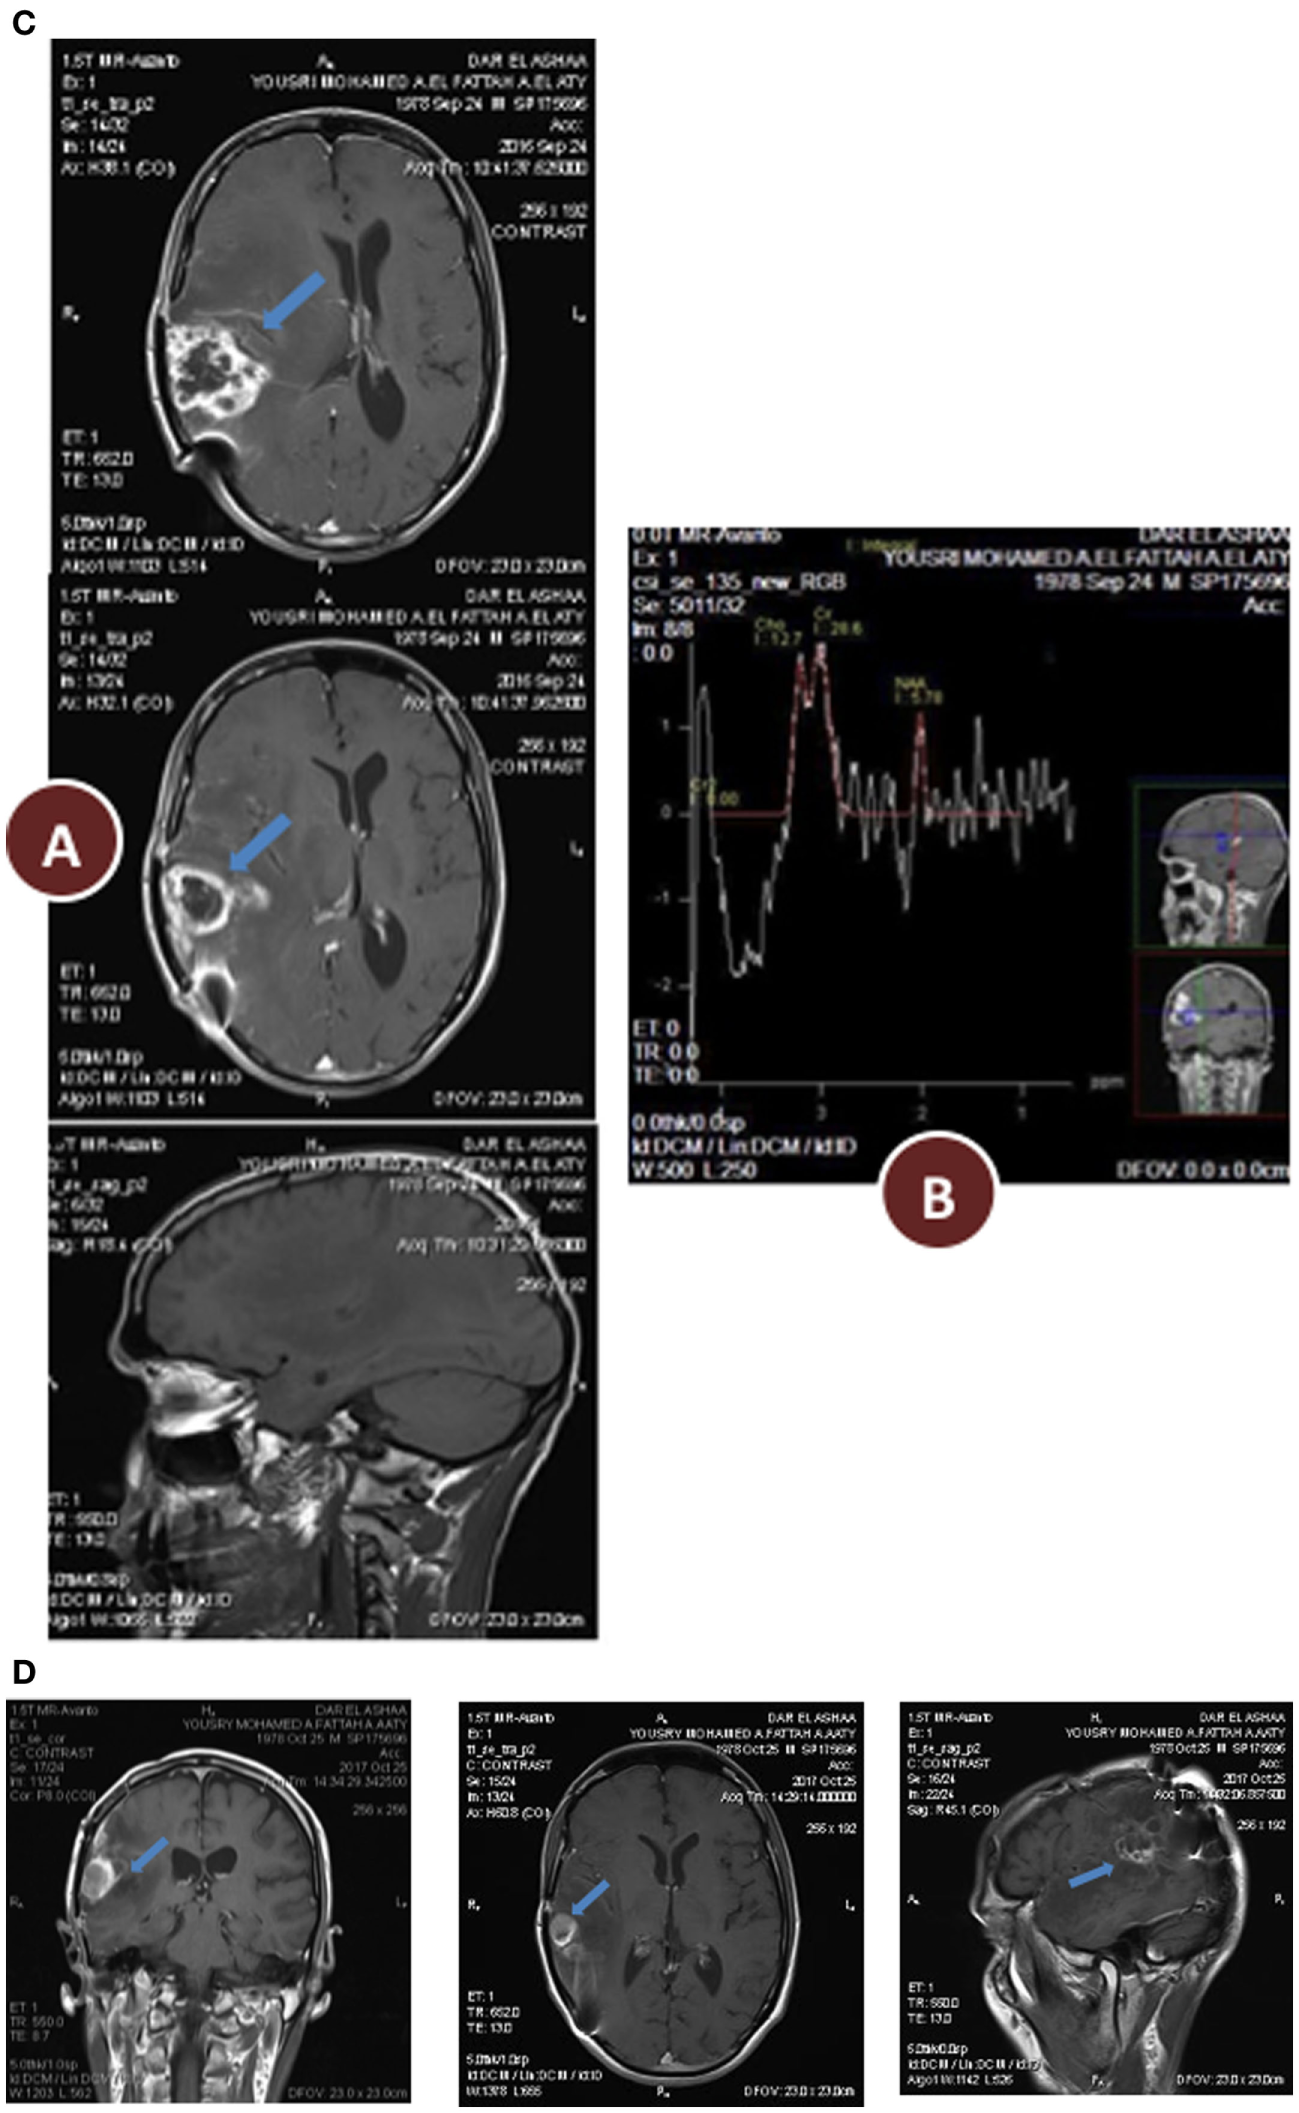

(A) Preoperative radiology, (A) magnetic resonance imaging (MRI) contrast enhanced images axial and sagittal view revealed cystic lesion with perifocal edema “blue arrow” and midline shift “red arrow”; (B) magnetic resonance spectroscopy (MRS) of the lesion revealed high choline value (28) and low N-acetylaspartate (NAA) value (2.7); (C) Functional MRI showed affection of motor and sensory functions; (D) MRI tractography showed displaced motor and sensory fibers. (B) 3 months postoperative radiology (A) MRI contrast enhanced images axial and sagittal view revealed reduction in tumor size and perifocal edema with less midline shift; (B) MRS of the lesion revealed reduction of choline value (21) and elevation of NAA value (3.5) compare to preoperative study. (C) 12 months postoperative radiology (A) MRI contrast enhanced images axial and sagittal view revealed stationary or slightly decrease in tumor size and less perifocal edema with less midline shift; (B) MRS of the lesion revealed reduction of choline value (19) and elevation of NAA value (4) compare to previous study. (D) Postoperative radiology at 20 months. MRI contrast enhanced images for axial, sagittal, and coronal views revealed further reduction in tumor size, with no perifocal edema or midline shift.

Enhanced brain MRI and magnetic resonance spectroscopy (MRS) evaluated 3 months postoperative and before radiation or chemotherapy revealed a stationary course of disease regarding tumor size that persisted to 12 months (Figures 2B,C). The choline creatine ratio on MRS indicated significant reduction in tumor metabolism (Figure 4A). The patient was neurologically intact and free of clinical seizure activity using only levetiracetam (1,500 mg/day) and KD. Fasting glucose was 60–70 mg/dL with ++ to +++ urine ketone levels and producing approximate GKI value of 1.8. Circulating insulin was low (approximately 4 IU) compared with the initial assessment (13 IU). The patient’s body weight was 67.7 kg with a BMI of 23.7. Radiotherapy with oral TMZ (75 mg/m2 orally once a day for 42 days) was initiated 18 h after water-only fasting (no food was consumed for up to 8 h following RT and TMZ). The patient also received 20 sessions of HBOT (2.5 ATA, 5 days/week, for 60 min/session). The L/P ratio, known to be elevated in GBM patients, was measured every week and sessions were repeated whenever L/P ratio increased (61). HBOT was also used to help lower the L/P ratio within normal limits (62, 63). The L/P ratio is also a good serum indicator for HBOT effectiveness on tumor oxygenation, glucose metabolism, and tumor redox state.

After 20 months of metabolic therapy and completion of radio and chemotherapy, the patient’s weight was 66.2 kg (BMI 23.2). Enhanced brain MRI and MRS revealed decrease in tumor size of about 1.5 cm in each diameter, with minimal perfusion and low metabolic activity assessed from the choline to creatine and choline to N-acetylaspartate (NAA) ratios on MRS (Figure 2D). Fasting insulin, glucose, and urine ketones were 2.1 IU, 65 mg/dL, and + to ++, respectively, producing an approximate GKI of 5.0 (Table 1). Also seen were further decreases in choline and increase in NAA with no midline shift or brain edema (Figure 2D), A reduction in tumor size was correlated with a correction of the midline shift after 20 months of treatment (Figure 4B). The patient remains in good health with no noticeable clinical or neurological deficits (Karnofsky Score, 100%).